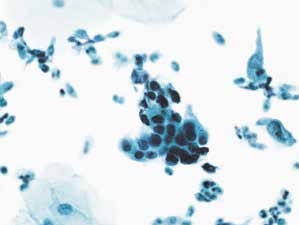

图4-31 高度鳞状上皮内病变(HSIL)(高倍、液基、巴氏染色)

异型增生的细胞密集成团,胞核明显增大,核膜不规则,核质比明显增高。